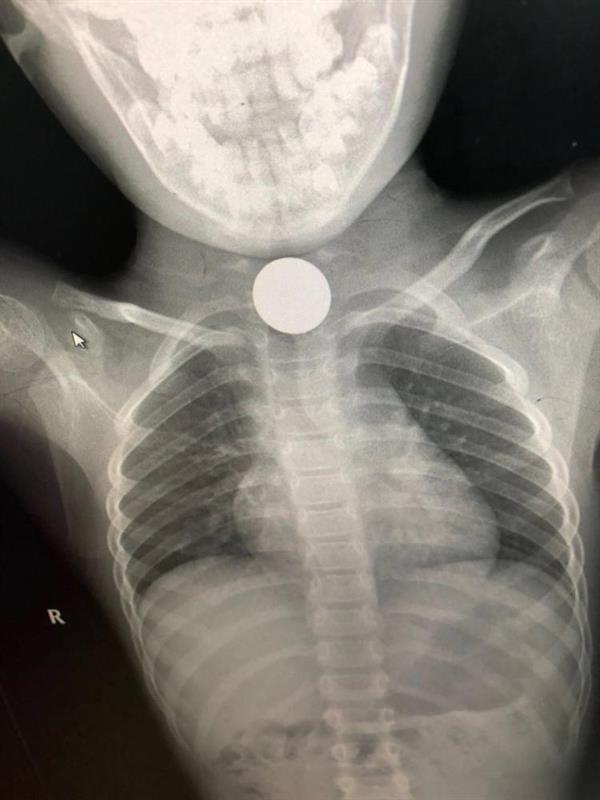

تمكن فريق طبي بمستشفى القريات العام من استخراج جسم معدني من مريء طفلة تبلغ من العمر خمس سنوات، من خلال عملية جراحية.

وقالت صحة القريات إن الأطباء قرروا إجراء العملية للطفلة بعد أن أظهرت صور الأشعة التي أجريت لها وجود جسم معدي غريب في الجزء الأعلى من المريء، مبينة أن العملية تمت بنجاح، وأن الطفلة الآن بحالة جيدة.